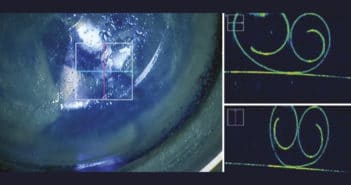

Quand les cellules visuelles ont disparu, on pourra imaginer l’utilisation de cellules souches rétiniennes en cours de développement mais, pour l’instant, la seule alternative aux stades terminaux est l’utilisation de photorécepteurs artificiels quand il n’y a plus aucune vision centrale. Tous les patients devraient bénéficier d’une rééducation basse vision dès qu’une gêne est notée, améliorant souvent la qualité de vie.